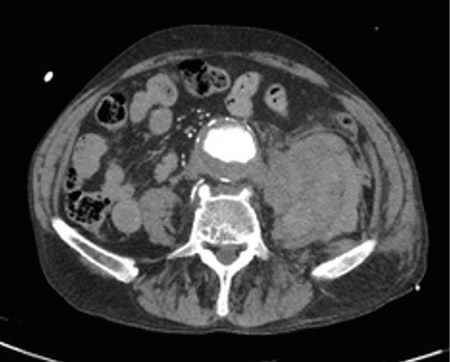

Respecto a las pruebas complementarias, en la analítica sanguínea, se halla una PCR de 39,1 mg/l, leucocitosis de 21.300/mm3, con 88 % de neutrófilos, y una hemoglobina de 10,5 g/dl. En la radiografía pélvica no se evidencian hallazgos patológicos. Debido a la hipotensión, se decide realizar un TC abdominal (Figuras 1 y 2), en el que se objetiva un aneurisma de aorta infrarrenal roto, con diámetro de 50 x 52 x 48 milímetros, a 50 mm de arteria renal derecha y a 65 mm de arteria renal izquierda, craneal a la bifurcación ilíaca. Asimismo, se aprecia un hematoma retroperitoneal en contexto de sangrado en parte posterior de la aorta, que infiltra el músculo psoas ilíaco izquierdo, justificando la clínica de coxalgia con irradiación izquierda. Se contacta con cirugía vascular, interviniéndose de forma urgente, con buena evolución posterior.

Fig. 1. TC coronal de aneurisma de aorta abdominal.

Fig. 2. TC transversal de aneurisma de aorta abdominal.